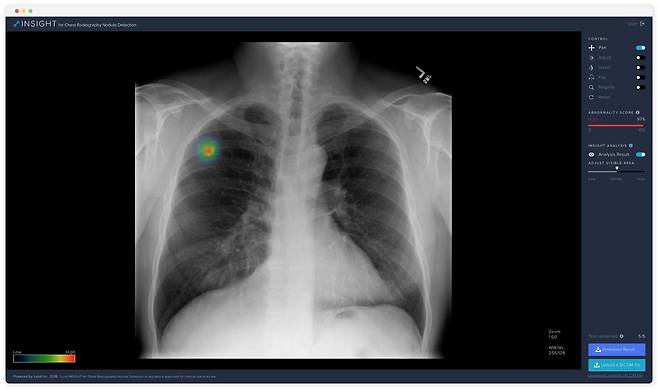

<루닛의 AI 기술을 적용, 흉부 엑스레이 영상에서 폐 결절 의심 부위를 검출할 수 있다>

엑스레이는 3D 오브젝트를 2D 이미지로 바꾸는 형태라 기존의 분석방식으로는 20~30%의 폐암환자를 놓칠 정도로 한계가 분명했다. 루닛의 솔루션이 결합되면 예전에는 보기 힘들었던 주요 포인트를 짚어주므로 진단의 정확도를 높일 수 있다. 굳이 말하자면 엑스레이 내비게이션이라고 할 수 있다.